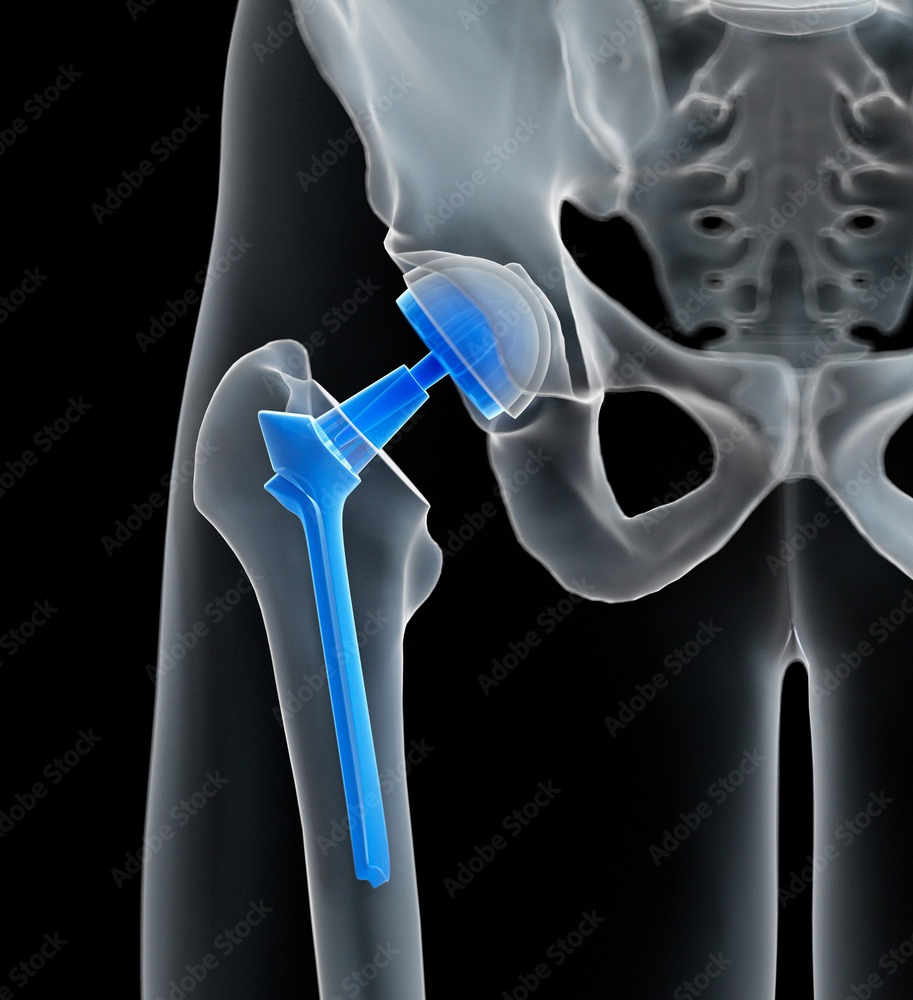

ENDOPROTEZOPLASTYKA STAWU BIODROWEGO

Ostateczna metoda leczenia operacyjnego zaawansowanych zmian zwyrodnieniowych stawu biodrowego. Wiąże się z resekcją nieodwracalnie zmienionych chorobowo powierzchni stawowych i zastąpieniu ich sztucznymi, wewnętrznymi protezami. Współpracujemy z liderami na rynku producentów protez aby zaproponować naszym pacjentom najlepsze i indywidualnie dobrane protezy charakteryzujące się długą przeżywalnością i odtworzeniem optymalnego zakresu ruchu . Zabieg ma na celu uwolnienie od dolegliwości bólowych pacjenta a także poprawę lub przywrócenie funkcji operowanego stawu.